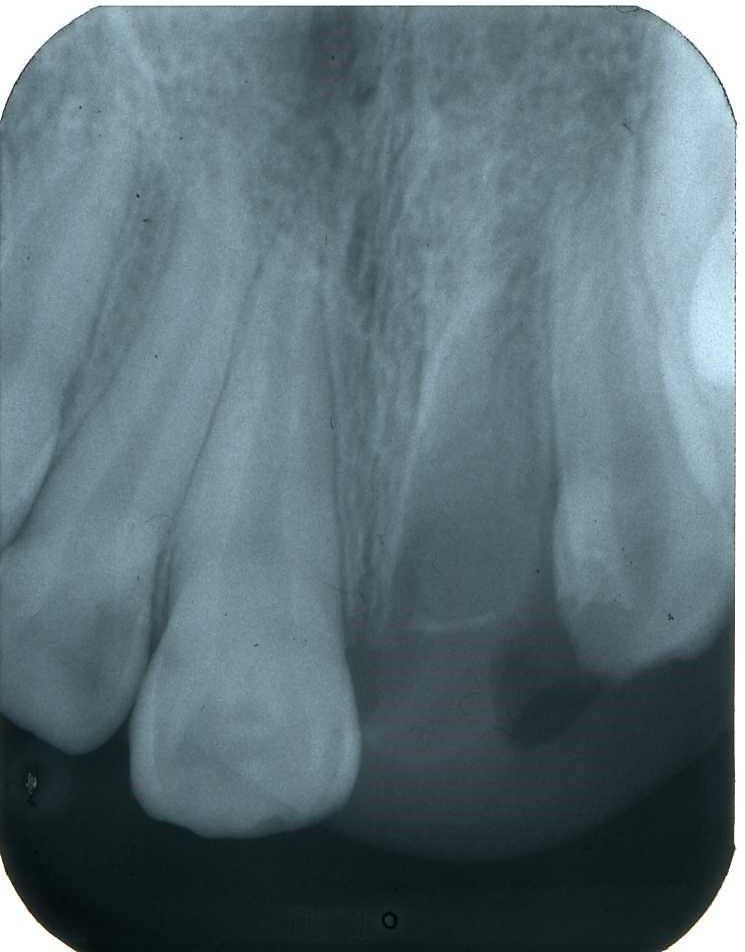

Radiograficamente è visibile il trattamento endodontico dell’incisivo laterale sinistro coinvolto anch’esso nel trauma. Sono visibili inoltre i dispositivi ortodontici necessari pe la sua estrusione al fine di recuperare l’ampiezza biologica, ovvero al fine di mantenere tre millimetri di tessuto dentale sano oltre il margine gengivale

Immagini radiografiche successive è possibile seguire negli anni l’evoluzione del dente reimpiantato. Nel corso degli la radice dell’incisivo centrale è andata in contro ad un progressivo riassorbimento per un atteso fenomeno di anchilosi.

L’anchilosi è un processo biologico infiammatorio che si verifica una volta che le fibre del legamento parodontale sono andate in necrosi e la superficie del cemento che ricompre la radice viene in contatto diretto con l’osso alveolare. In questa circostanza si attiva nei macrofagi una differenziazione in senso osteoclastico e dentino clastico che in pochi anni, talvolta in pochi mesi, porta al completo riassorbimento della radice e quindi alla sua scomparsa